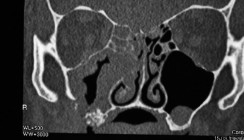

Die Anamnese ergab eine parodontale Vorbehandlung vor circa zehn Jahren. Der letzte Zahnarztbesuch lag ungefähr ein Jahr zurück. Damals seien keine Veränderungen festgestellt worden. Im weiteren Gespräch wurde die Patientin zu Allgemeinerkrankungen und verordneten Medikamenten befragt. Laut Angaben der Patientin litt sie unter Bluthochdruck und einer Herzinsuffizienz. Sie nahm die in Tabelle 1 aufgeführten Medikamente ein. Dabei sei während eines Krankenhausbesuches vor vier Monaten das Präparat Amlodipin erstmalig verordnet worden. Die Angaben wurden später durch Rücksprache mit der behandelnden Hausärztin verifiziert. Bei der klinischen Untersuchung zeigten sich generalisierte Gingivahyperplasien an allen Parodontien des Ober- und Unterkiefers (Abb. 1 und 2). Es lag eine generalisierte Gingivitis und plaqueinduzierte Parodontitis marginalis chronica vor, die durch die vorhandenen Pseudotaschen noch verstärkt wurde. Die geröteten und ödematös geschwollenen Pseudotaschen überlagerten partiell die Zahnkronen interdental, sodass traumatische Einbisse bei Interkuspidation bestanden. Teilweise entleerte sich Pus über die Pseudotaschen. Das angefertigte Orthopantomogramm bestätigte einen vertikalen und horizontalen Knochenabbau, ausgelöst durch die parodontale Vorerkrankung. Es wurde die klinische Verdachtsdiagnose einer Amlodipin-induzierten Gingivahyperplasie bei generalisierter Parodontitis marginalis chronica gestellt. Aufgrund des Alters der Patientin und der bestehenden Vorerkrankungen wurde ein minimalinvasives Vorgehen favorisiert. Dazu wurde eine vorsichtige Entfernung des vorhandenen Zahnsteins vorgenommen. Die Pseudotaschen wurden mit Chlorhexidinlösung gespült und der Patientin die Anwendung von Chlorhexidinlösung zur Mundspülung verordnet. In einer zweiten Sitzung wurde zu differenzialdiagnostischen Zwecken eine Probeexzision im Unterkiefer-Prämolarenbereich rechts durchgeführt. Das histologische Ergebnis bestätigte das Vorliegen einer Gingivahyperplasie. Nach Rücksprache mit der behandelnden Hausärztin konnte ein Absetzen der Medikation von Amlodipin vorgenommen werden. Die Patientin wurde nach einem und drei Monaten nachkontrolliert. In diesem Zeitraum kam es zu einer Reduktion der Hyperplasie und subjektiv deutlicher Beschwerdebesserung. Es lagen deutlich reizlosere gingivale Verhältnisse im Vergleich zur Erstuntersuchung vor (Abb. 3 und 4). Eine Parodontalbehandlung wurde empfohlen. Zusätzlich vorliegende Ödeme der unteren Extremitäten hatten sich ebenfalls zurückgebildet.